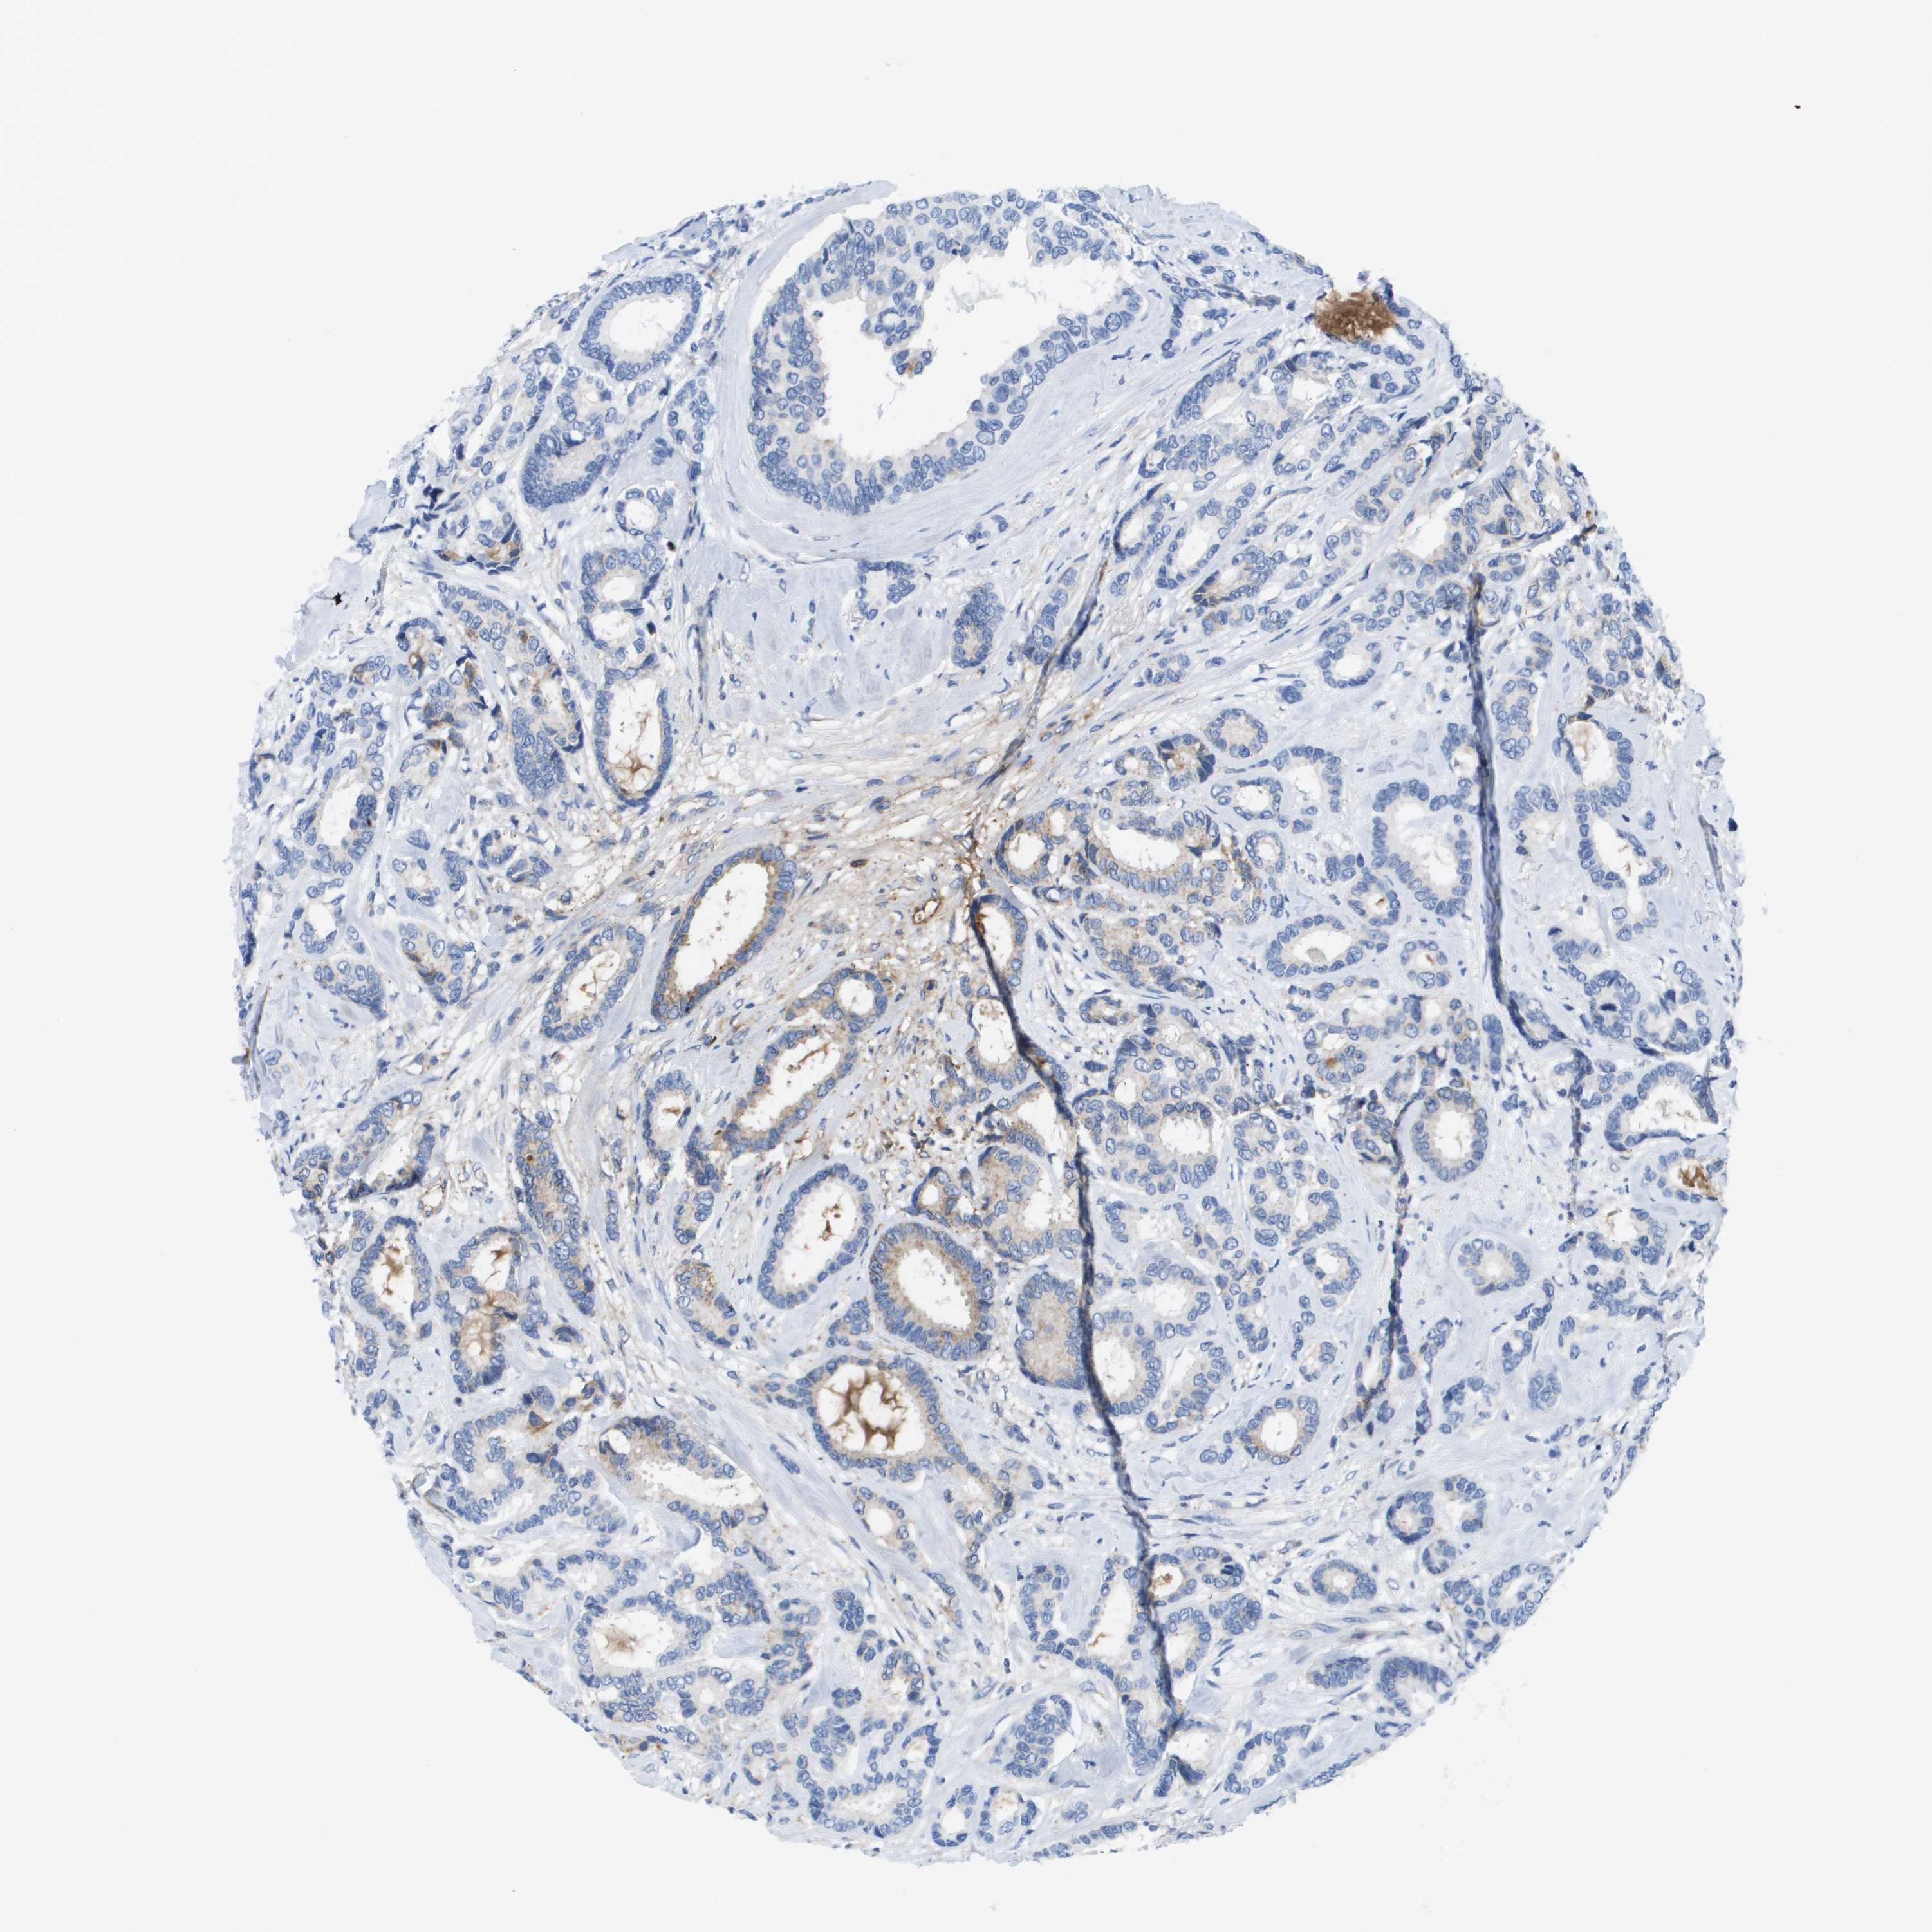

BRCA TCGA BRCA VALIDATION PROTEIN EXPRESSION

ANTIBODIES

AND

VALIDATION